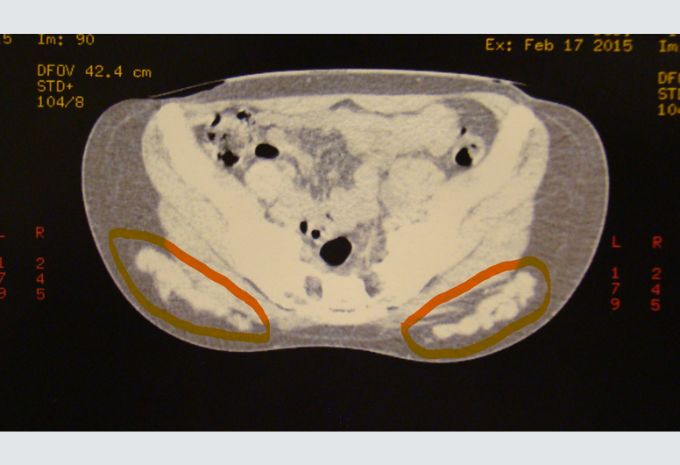

En las fotos se muestran granulomas con PMMA extraídos a paciente a la cual se la salvó de una posible insuficiencia renal y litiasis renal a repetición. En la imagen de la tomografía axial computada preoperatoria de la paciente se observa (ver círculos naranjas) la enorme cantidad de PMMA que tenía en su cuerpo.